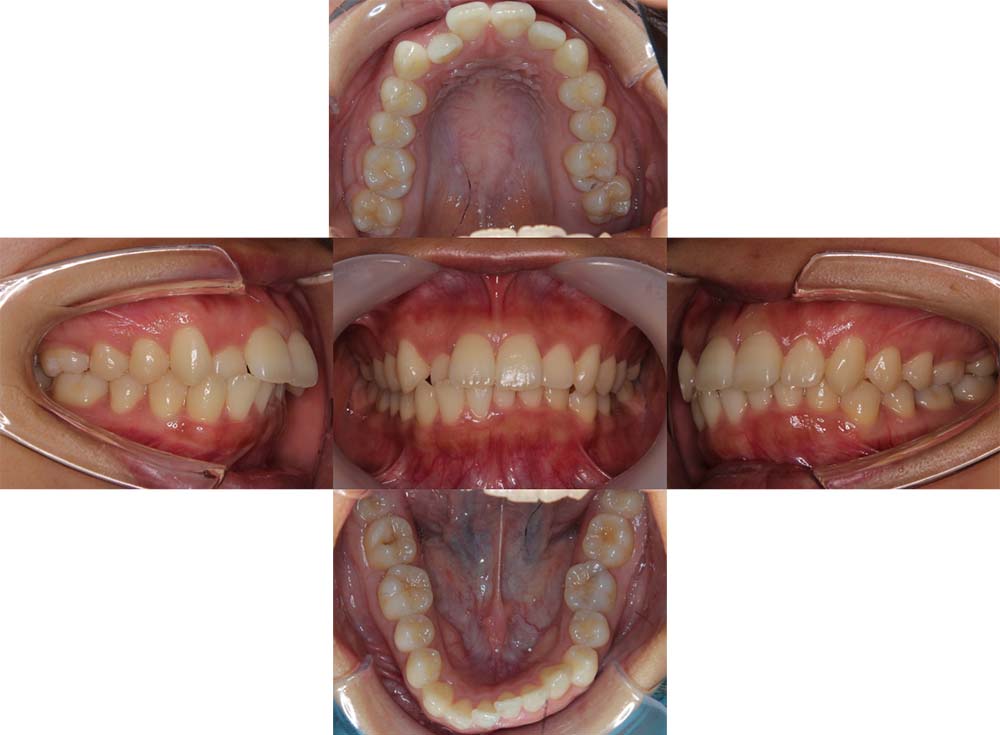

症例02

| 主訴 | 下あご顎が出ている。曲がっている。 |

| 診断名あるいは主な症状 | 反対咬合、非対称、空隙歯列、過蓋咬合 |

| 年齢/性別 | 19歳・女性 |

| 矯正ステージ | 大人の矯正治療 |

| 治療方法 | ワイヤー矯正、顎矯正手術の施行 |

| 抜歯部位/抜歯有無 | 非抜歯 |

| 治療内容 | 上下顎歯列を並べた後に顎矯正手術の施行。 |

| 費用 | 保険治療 |

| 治療期間 | 3年2ヶ月 |

| 主なリスク・副作用 | 痛み、歯根吸収、歯肉退縮、虫歯、後戻り |